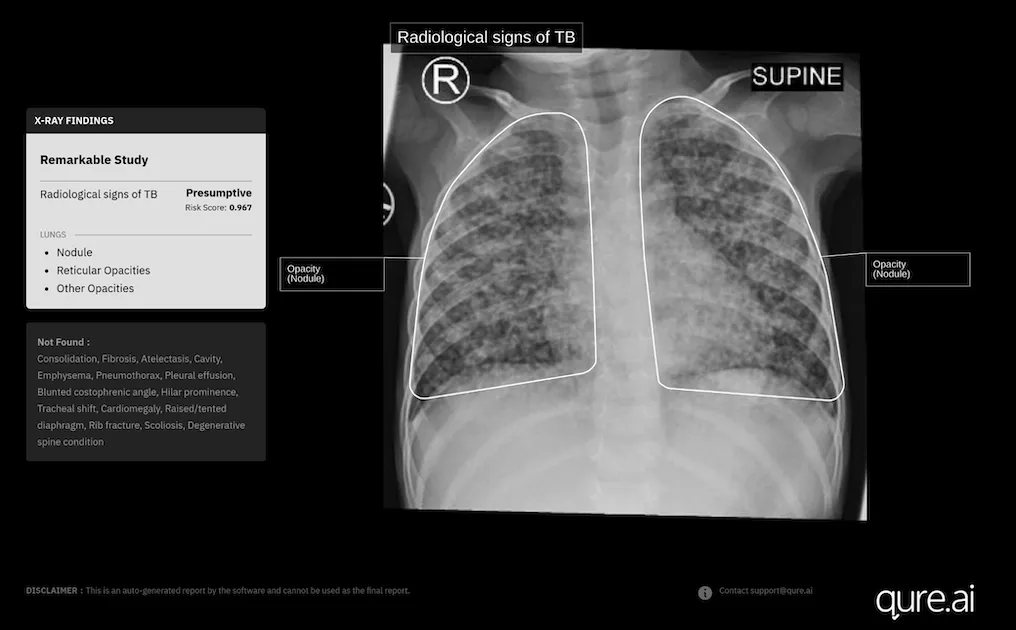

Photo courtesy of Qure.ai

It has recently received a new CE Mark under the European Union's Medical Device Regulation for the use of its AI-powered chest X-ray software, qXR, in children aged 0-3 years.

Last year, Qure.ai further trained qXR with more paediatric data – chest X-rays from children aged 0-15 years paired with corresponding GeneXpert results collected from several high TB-burden countries.

"We gathered thousands of these X-rays and retrained the model to capture the subtle and often non-specific patterns seen in younger children, particularly those under five," Divya Gupta, Chief Business Officer – Global Health at Qure.ai, told Mobihealth News in an email interview.

The model demonstrated a "marked increase in accuracy across all paediatric groups," she noted. Retrospective and prospective studies done after an internal validation and initial deployments at select global sites also showed "highly encouraging results." Qure.ai is set to report findings from a large-scale internal validation at a global conference on lung health in Denmark later in November.

"Preliminary analyses from earlier test sets have already shown a 20% improvement in diagnostic accuracy against GeneXpert results after incorporating paediatric data into the model," Gupta added.